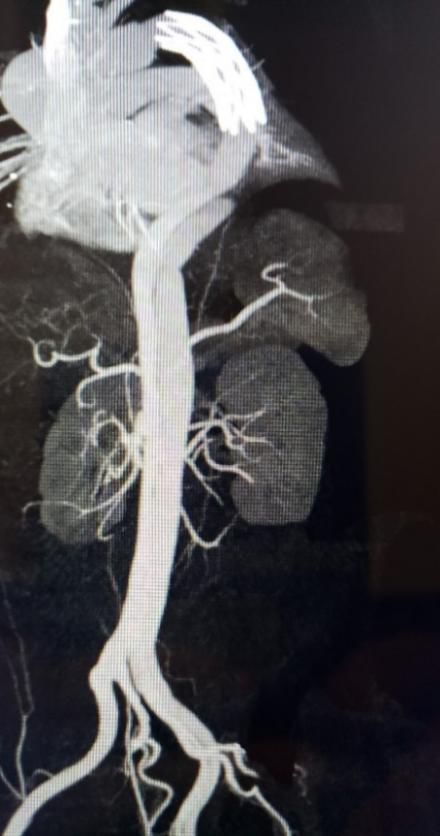

目前,患者行术后1月随访发现,所有重要分支均保持通畅,主动脉真腔明显扩大,环主动脉最大直径缩减(图1)。

图1 术后造影显示真腔明显扩张

术前全主动脉三维重建

术后一个月

全主动脉三维重建